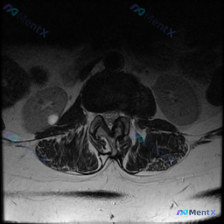

刚看到这份腰椎MRI T2轴位影像,整理了完整的分析思路分享给大家,一起交流一下。 基本影像信息 这是一份腰椎椎间盘水平的MRI T2序列轴位图像,关键观察结果如下: 1. 椎间盘:位于图像中央,髓核信号强度减低(T2像呈灰黑色),提示脱水退变,后缘可见局限性向后突出,边缘形态欠规整 2. 椎管与硬...